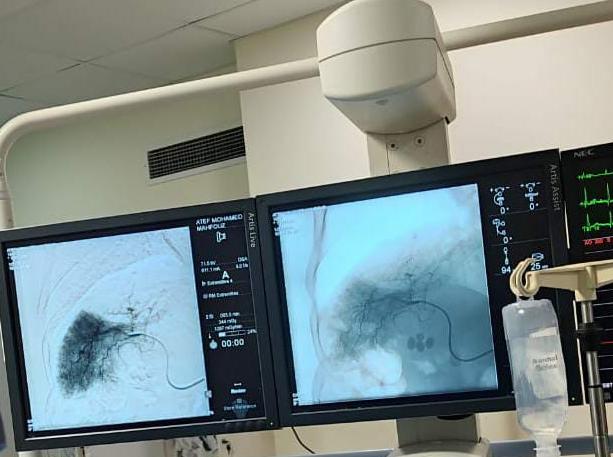

الأجهزة الطبية المستخدمة

وأضافت، أنه يتم الحقن الشرياني باستخدام الأشعة التداخلية للكبد عن طريق القسطرة التداخلية للشريان الكبدي من خلال عمل فتحة صغيرة في الجلد لا تتعدى الـ 2 مم يتم عن طريقها الحقن الكيماوي وسد الشريان المغذي للورم مباشرة؛ والذي يؤدي إلى ضمور الورم ويساعد في التخلص من أورام الكبد نهائيًا.